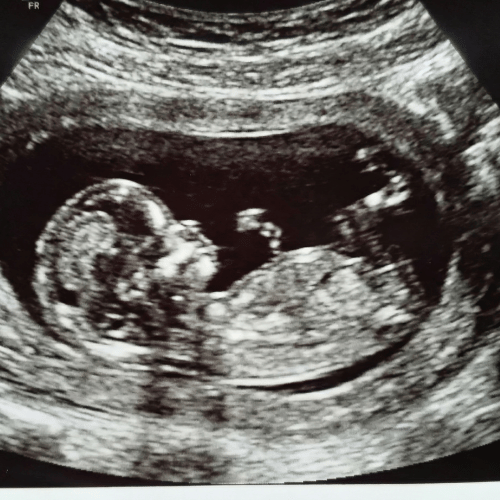

kinesiologie enceinte, échographie bébé